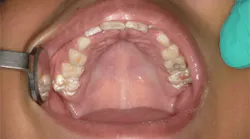

Commercially available as Advantage Arrest by Elevate Oral Care (i), 38% silver diamine fluoride is approved by the Food and Drug Administration (FDA) for the reduction of dentinal hypersensitivity, but it has also been shown to reduce bacteria and matrix metalloproteinases (MMPs), which are responsible for the degradation of dentin, and it is believed to arrest carious lesions. (2–6) In addition to using it to treat dentinal hypersensitivity, dentists are using it off-label to arrest carious lesions and as a diagnostic indicator. (7) Silver diamine fluoride will only stain defects in the tooth structure, such as carious lesions and restorative margins; sound tooth structure will not be stained by silver diamine fluoride. In addition, silver diamine fluoride is very cost effective as one drop can be used for multiple teeth.

- Educate your patients. Silver diamine fluoride will stain carious tooth structure a dark brown or black color. Caution should be used on other tooth surfaces and near the margins of composite restorations or crowns. Explain the risks of discoloration to tooth structure before application. If a restoration is stained, the stain should polish off, but staining around margins may remain.